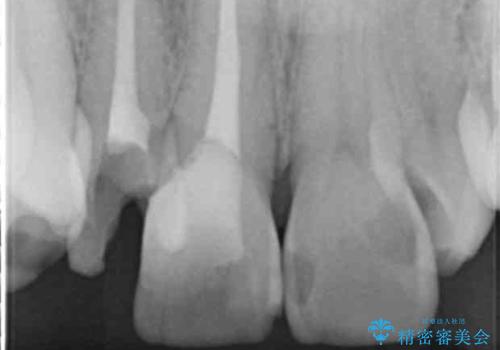

小臼歯の歯根長が長いことを治療前にレントゲンで確認し抜歯部位を決定しました。

患者様の「できるだけ短期間で治療を終わらせたい、セラミックが入れられたら良いので大がかりなことはしたくない」とのご要望により、3Dシミュレーションを何度も行い患者様とのコンサルを重ね、上顎左右犬歯と左下2を抜歯して②のプランである補綴前矯正(インビザライン)を行うことにしました。

犬歯は歯根が長く寿命も長い歯で、咀嚼機能時も重要な役目を果たすため、基本的に矯正の便宜抜歯に選択する歯ではありません。(一般的には第一小臼歯もしくは第二小臼歯が選択されることが多いです)